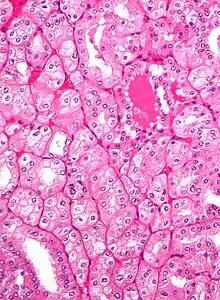

| Micrograph of a renal oncocytoma. |

A renal oncocytoma is a tumour of the kidney made up of oncocytes, epithelial cells with an excess amount of mitochondria.[1][2]

Renal oncocytoma is thought to arise from the intercalated cells of collecting ducts of the kidney. It represent 5% to 15% of surgically resected renal neoplasms. Ultrastructurally, the eosinophilic cells have numerous mitochondria.

An oncocytoma is an epithelial tumor composed of oncocytes, large eosinophilic cells having small, round, benign-appearing nuclei with large nucleoli and excessive amounts of mitochondria.